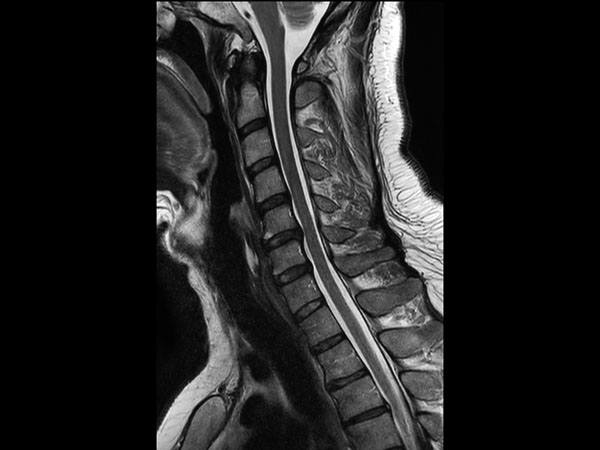

Comprehensive Cervical Spine imaging at 3.0T